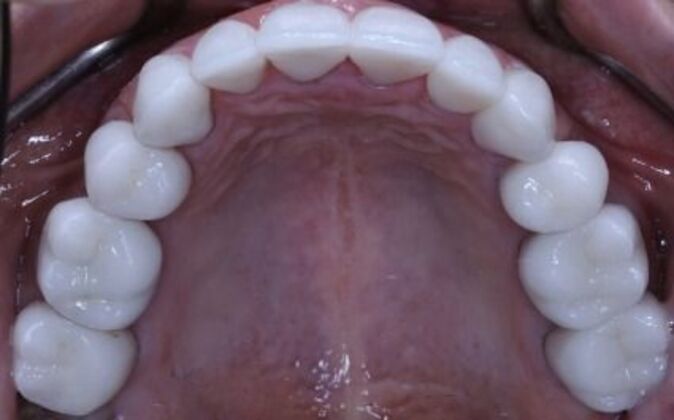

Full Mouth Reconstruction: Risa

Description

Full mouth reconstruction. When you see a client at a young age with so much dental work to begin with you consider your options carefully. You need to be aggressive in approach and conservative in maintaining as much of the healthy tooth structure. Have to consider the age of a patient whenever you embark on a major dental work especially when it involves redoing everything, repositioning and re-establishing a brand new bite position and correcting the inflammatory gum response from previous dental work. You cannot approach a case like this with a limited treatment plan that only addresses a few teeth. If this case is treated one tooth at a time you may leave the patient a “dental cripple”. By that I mean that this patient will constantly be at dental offices for the rest of her life addressing one broken down tooth after another until a cascading domino effect will render all the teeth in a hopeless condition. Here is a situation where we are dealing with multiple problems 1-bite collapse and malfunction 2-gum disease exacerbated by poorly fitting crowns 3-decaying teeth affecting the health of the roots This case had to consider all of these issues. Must understand that this patient is very young and has many years ahead of her so the dentistry has to be done meticulously, conservatively,aggressively and expeditiously. It’s a tough balancing act but as dentists we need to be realistic about our treatment objectives and have a proper plan that addresses dental breakdown. We were able to achieve the esthetic and functional concerns of the patient. Although we felt the color of the teeth were too bright. We do need to consider patients desires since they need to live with this for the rest of their lives and ultimately they need to be happy